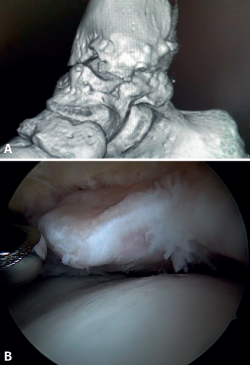

El PAT óseo por osteofitos también ha sido relacionado con la presencia de inestabilidad crónica. Se ha postulado que la alteración en la cinemática articular secundaria a la insuficiencia ligamentosa favorece el desarrollo de osteofitos en la región anterior de la tibia y el astrágalo(36,37). Estudios recientes han cuestionado la teoría de tracción capsular repetida como origen de los osteofitos en la práctica deportiva(38), ya que es fácilmente demostrable que los osteofitos se localizan intraarticulares por dentro de la inserción capsular, en el contexto de una artroscopia de tobillo (Figura 2). Por ello, la artroscopia con dorsiflexión de tobillo es fundamental para poder resecar los osteofitos de forma segura sin daño capsular ni a las estructuras suprayacentes, mientras que la técnica clásica de tracción (invasiva o no) dificultaría enormemente su resección, por lo que hoy en día se desaconseja su uso rutinario(3,39). Vega distingue dos tipos de osteofitos(3), según sean por trauma repetitivo (forma de pico) o por inestabilidad (en forma de visera). El concepto de microinestabilidad se asocia a microtraumatismos de repetición que podrían ser el origen de osteofitos con esta morfología característica (Figura 3).

La resección de osteofitos se realiza deslizándose desde su parte superior, rebajando gradualmente hasta alcanzar la zona articular (Figura 2). Con una pinza de tipo basket se puede resecar la zona más cercana a la articulación (Figura 5). Suele ser útil intercambiar los portales de visión y trabajo para visualizar y resecar completamente los osteofitos. Para el pinzamiento de partes blandas, un sinoviotomo de 3,8 o 4 mm suele ser suficiente. El vaporizador es útil en pinzamientos compactos, típicos de condiciones postraumáticas o reintervenciones, también para delimitar la parte ósea del osteofito antes de su resección.

Figura 2. Osteofito anterior de la tibia. A: en dorsiflexión la cápsula se separa del osteofito permitiendo su resección (B) mediante fresado.